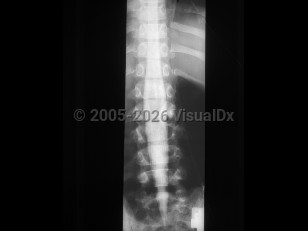

Diastematomyelia in Child

Diastematomyelia, split-cord malformation (SCM), is a rare congenital abnormality in which there is partial or complete cleft in the spinal cord by a sagittal osseous or fibrous septum. It is seen predominantly in females, most often affecting the lower thoracic or upper lumbar segments. Clinically, diastematomyelia often presents as tethered cord syndrome (back pain, abnormal gait, spasticity, bowel / bladder incontinence) in children or young adults, although symptom onset may occur at any age. Patients may have a midline cutaneous abnormality such as a hairy patch or dimple over the affected area. There are two classifications:

- SCM type 1 consists of two hemicords, each with its own dural sheath, separated by a bony or cartilaginous septum.

- SCM type 2 consists of two hemicords within the same dural sheath but separated by a fibrous septum.